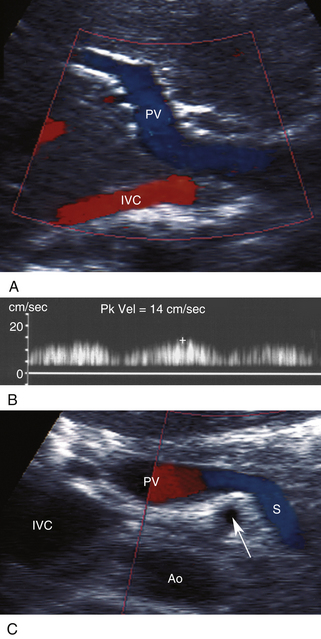

Допплеровская оценка кровотока в воротной вене обычно проводится вдоль длинной оси воротной вены, как показано на рисунке 26-9 . Ток в воротной вене и ее притоках обычно направлен в сторону печени (гепатопетальный). Кривые допплерографии воротной вены демонстрируют тонкие фазовые вариации, вызванные изменениями давления и сократимости сердца, связанными с дыханием. Фазический паттерн генерирует звук «бури» в слышимом допплеровском сигнале, который совершенно отличается от пульсирующего звука печеночной артерии и других артериальных ветвей. Ток однонаправленный в сторону печени и по внешнему виду аналогичен венам нижних конечностей. При правожелудочковой недостаточности и перегрузке жидкостью пульсация правого предсердия может передаваться через печень в воротную вену, которая затем демонстрирует пульсирующие допплеровские сигналы. Эти волны могут быть двунаправленными и выглядеть «артериальными», но они не следуют за систолой сердца.

РИСУНОК 26-9. Ультразвуковое исследование воротной вены и ее притоков. А. Длинноосевой вид воротной вены (PV). НПВ, нижняя полая вена. Б — нормальный фазовый допплеровский спектр воротной вены. Пиковая скорость (Pk Vel) составляет 14 см/сек. C. Селезеночная вена (S) видна в месте ее соединения с воротной веной (PV). Стрелка представляет верхнюю брыжеечную артерию. Ао, аорта; НПВ, нижняя полая вена.

Нормальная воротная вена имеет диаметр до 13 мм при спокойном дыхании у лежачего пациента. Калибр воротной вены и ее притоков обычно существенно увеличивается во время длительного глубокого вдоха. Лучше всего это заметно в селезеночных и верхних брыжеечных венах, диаметр которых обычно увеличивается на 50–100% от спокойного дыхания до глубокого вдоха. При портальной гипертензии воротная вена может расширяться, а дыхательные изменения в воротной и селезеночной/верхней брыжеечной венах могут быть облитерированы.